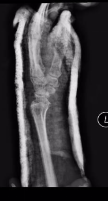

术后第一天,患者意识恢复清醒,复查头部CT提示颅内血肿清除彻底。全腹CT、双腕关节CT显示:肠管管壁明显水肿增厚,邻近肠系膜肿胀,肠间隙模糊,盆腔少量积液,腹腔内未见游离积气,提示肠管或肠系膜损伤;右侧月骨脱位,左侧桡骨远端骨折。

胃肠小儿外科、脊柱创伤外科会诊讨论,确定了分期治疗方案。术后第2天,胃肠小儿外科张达主任医师在全麻下为患者行小肠破裂修补术+腹腔脓肿清除术+肠粘连松解术+肠排列术。脊柱创伤外科薛建康主任医师为患者行左侧桡骨骨质手法复位后石膏外固定,后行右月骨脱位切开复位。

(左侧桡骨远端骨折) (手法复位及石膏外固定后位置良好)